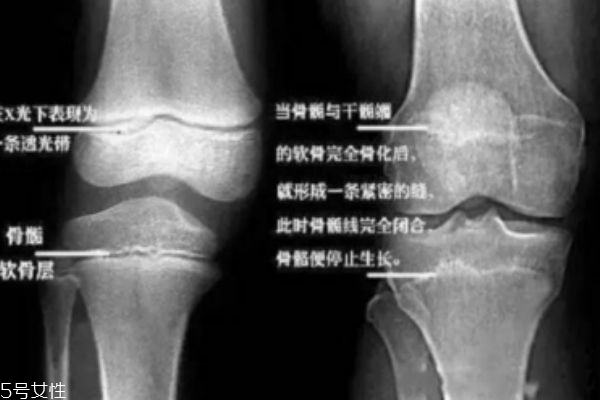

取決于骨骺線(記住它,它是你長高的關(guān)鍵)是否閉合。人體的長高,是全身性的增長,其中最突出的是四肢,尤其是下肢的增長。也就是說,一個(gè)人能長到多高,下肢的長骨起了決定性的作用。人在剛出生時(shí),長骨的骨干大部分已經(jīng)骨化,但四肢長骨的兩端還有未骨化的骨骺。骨骺和骨干之間有一層軟骨層,醫(yī)學(xué)上稱之為骺軟骨,即骺板,也叫骨骺線。當(dāng)骺板不斷變薄,最后消失,也就是骨骺與骨干完全閉合時(shí),就完成了骨的發(fā)育。自此,人就不能再長高了……不能再長高了……長高了……我猜你更想問:怎么知道自己的骨骺線閉合了沒呀?很簡單,去醫(yī)院給膝關(guān)節(jié)拍張X光片就一清二楚了。骨骺線還透亮透亮的?恭喜你!你還能再搶救一下!